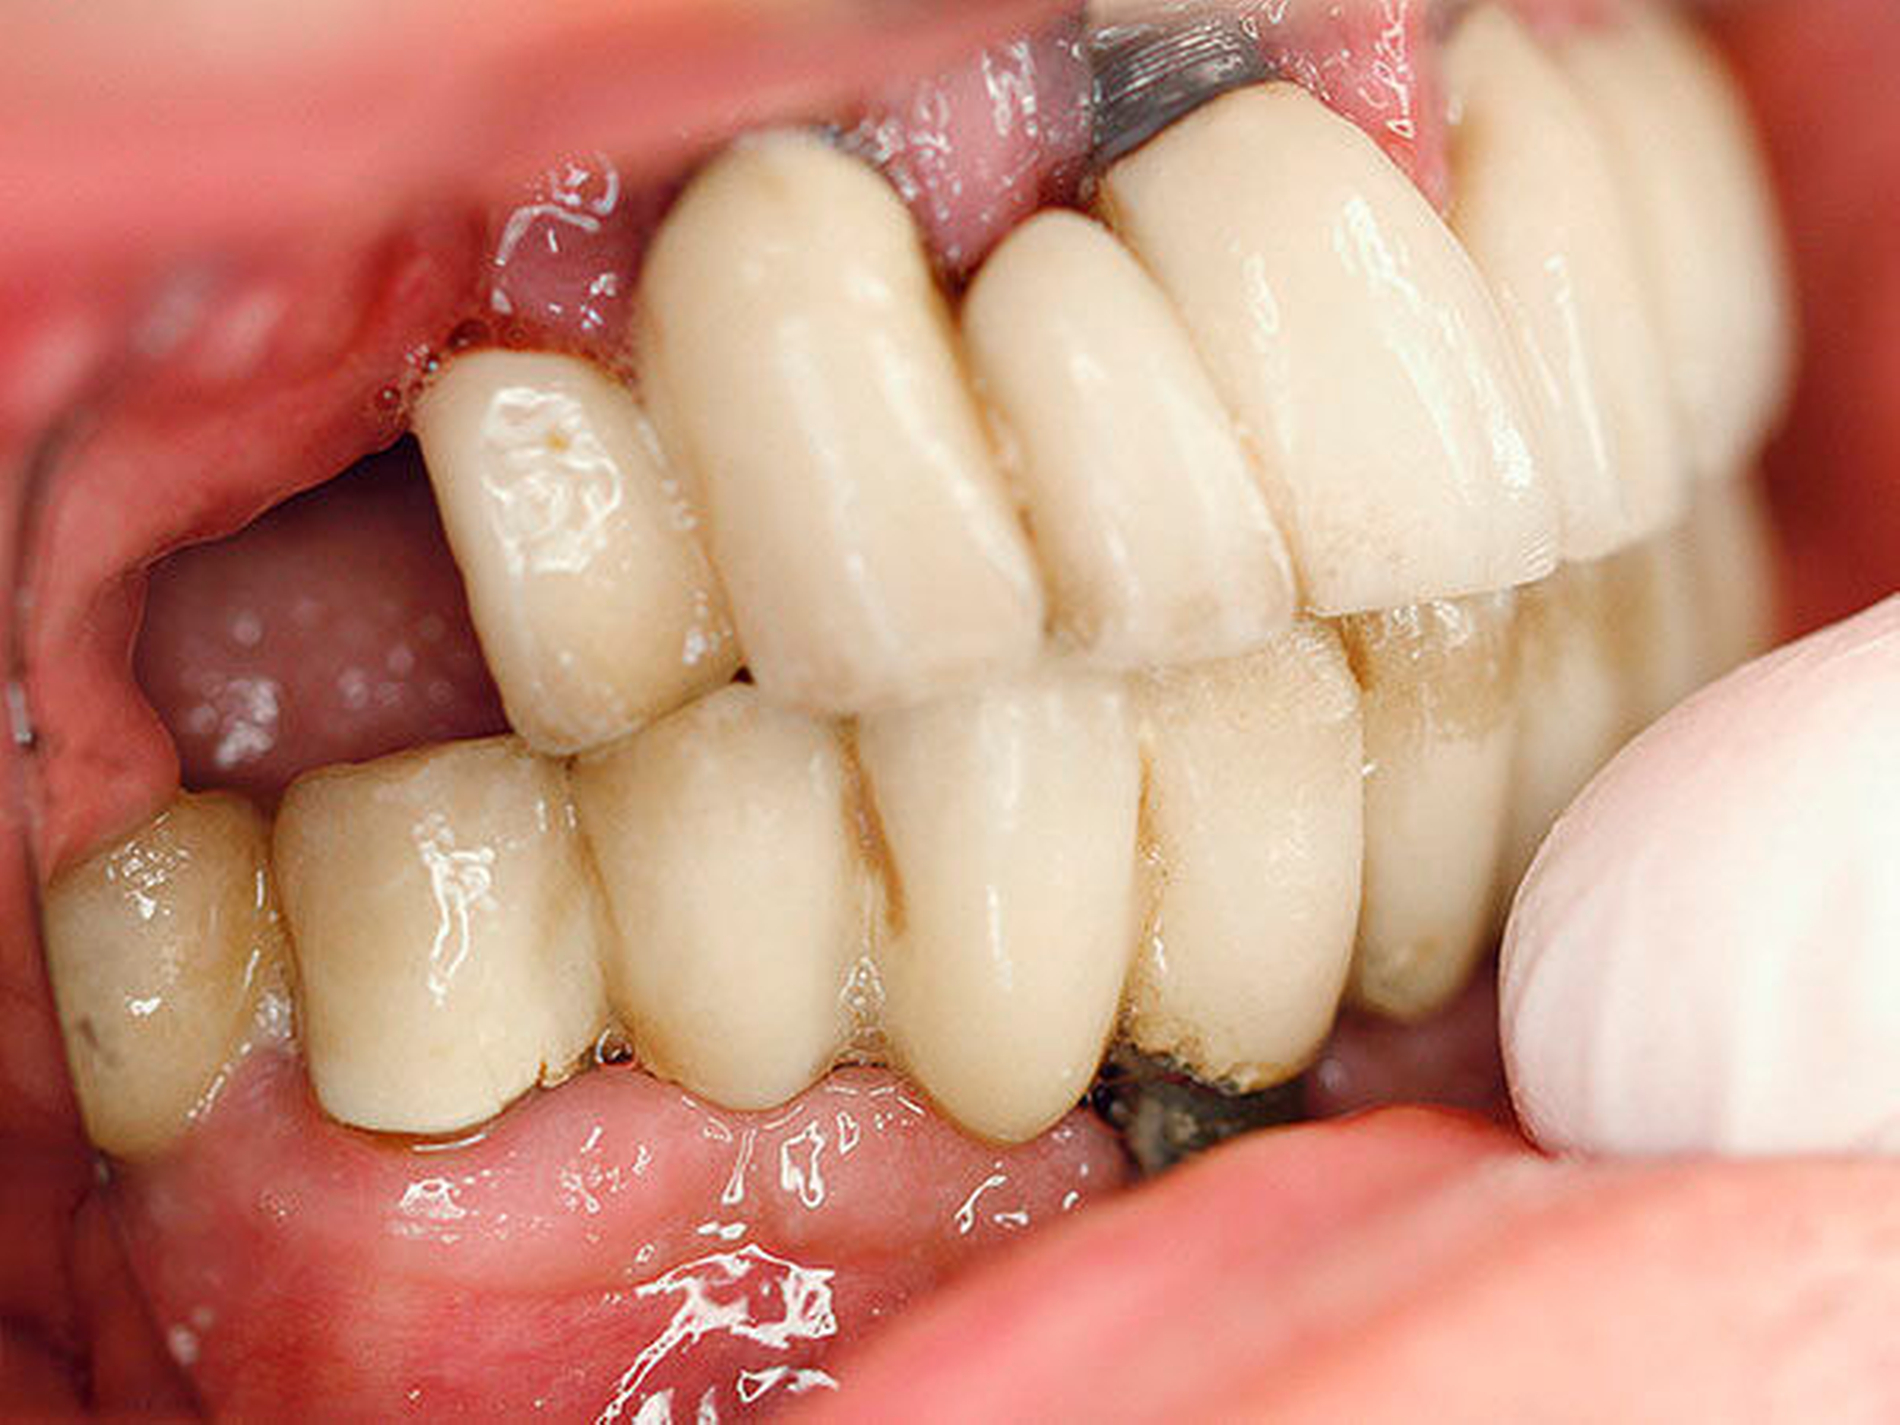

Intraoral zeigten sich implantatgetragene Kronen-Brückenkonstruktionen im Ober- und im Unterkiefer. Diese waren initial sowohl im Ober- als auch im Unterkiefer auf jeweils vier Implantaten befestigt. Im Bereich des rechten Oberkiefers zeigte sich in Regio 16 eine Mund-Antrum-Verbindung, die offenbar nach dem Versuch einer primären plastischen Deckung weiterbestand. Es bestand eine breite Dehiszenz bis ins Kieferhöhlenlumen hinein. An allen Implantaten zeigte sich eine chronische Periimplantitis mit ausgeprägtem Knochenabbau und freiliegenden oberen Gewindegängen.